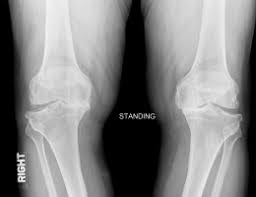

胫股关节痛表现为膝关节内外侧疼痛或全关节痛,不能长时间站立、行走,不能提重物。比较严重的患者我们会让他们站着拍摄X光片,常会发现膝关节胫股之间的间隙不等高了。这就意味着狭窄一侧的关节软骨及半月板严重磨损。当膝关节内侧软骨磨损严重时,患者两腿相并会在两膝之间出现很大的空隙,这就是俗称"罗圈腿",在老年偏胖的女性中常见。